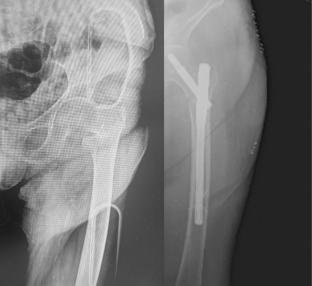

Abstract Image